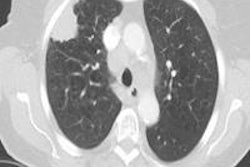

The use of new techniques and portable equipment have enabled the trust to increase the number of biopsies it performs each year tenfold, reducing patient admissions and cutting costs by about 90%, the hospital said. Introduction of the new technique is especially timely considering the increasing use of lung cancer screening with CT, the trust said.

Wider use of the technique could free up hundreds of hospital beds while allowing more patients to undergo diagnostic biopsy more quickly, leading to earlier lung cancer diagnosis.